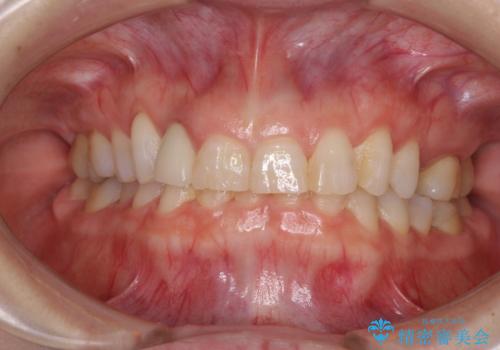

- 前歯のクラウン周りに歯肉が腫れていることを気にして来院された患者様です。

元々磨き残しによる歯肉の腫脹がありましたが、クラウンが歯肉深くに装着されていたため、特に腫脹が目立っていました。

仮歯に置き換えた際に歯周外科処置を行い、歯肉の腫脹が落ち着いたことを確認してオールセラミッククラウンにて補綴することとしました。

外科処置後の痛みを気にしていましたが、小規模の処置であったため、痛みを感じることはほとんどありませんでした。

気になっていた腫脹がなくなり、患者様には大変満足していただきました。